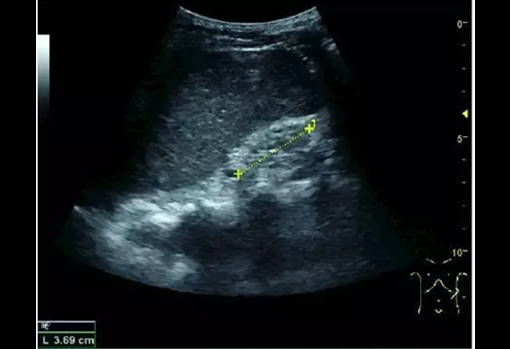

Ultrasound is an important method for diagnosing chronic kidney disease and judging prognosis. Whether it is glomerulosclerosis, tubular atrophy, interstitial fibrosis, or inflammation, echogenic cortical enhancement is seen on ultrasound imaging. Normal kidney echoes are similar to those of the liver or spleen. In addition, renal atrophy and cortical thinning are common, especially as the disease progresses. However, kidney size correlates with height, and patients with short stature have smaller kidneys; therefore, kidney size should not be used as the sole criterion.

Chronic kidney disease due to glomerulonephritis: thinning of the cortex and increased echogenicity. +, dotted line: kidney length